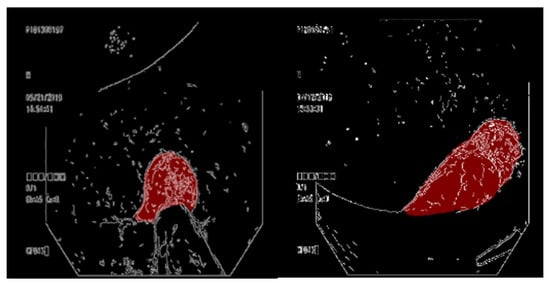

3.4. Overlaying a Contour Map on a Ground Truth Map

3.5. Overlaying the Ground Truth Map onto the Original Image

3.6. Conditional GAN Architecture

3.7. Comparison of GAN Output